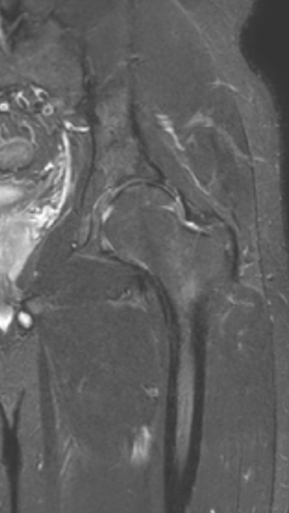

Асептический некроз тазобедренного сустава

3 процедуры ФДТ, 9 процедур MBST, 20 процедур ИПМТ

Параметры изменяются в зависимости от процедуры

Дата публикации: 22.08.2025 14:26:45